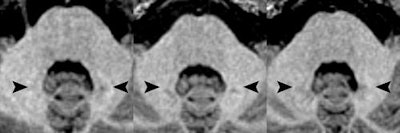

Axial MR images of a patient before (left) and after four (middle) and eight (right) administrations of the macrocyclic GBCA gadoterate meglumine. Location of the hyperintense dentate nucleus (arrowheads) is evident, with the patient's pre-existing hyperintensities due to 14 prior administrations of linear GBCAs. Images courtesy of Radiology.Study strengths